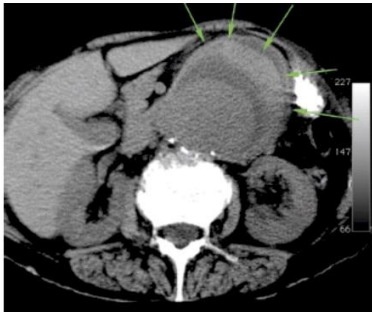

O cirurgião vascular deverá dominar este método de diagnóstico por imagem que poderá ser útil tanto no diagnóstico como no planejamento do tratamento, um dos sinais de ruptura é visibilizado na figura acima, que sinal é esse?